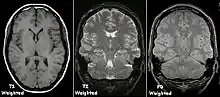

T1 and T2

Each tissue returns to its equilibrium state after excitation by the independent relaxation processes of T1 (spin-lattice; that is, magnetization in the same direction as the static magnetic field) and T2 (spin-spin; transverse to the static magnetic field). To create a T1-weighted image, magnetization is allowed to recover before measuring the MR signal by changing the repetition time (TR). This image weighting is useful for assessing the cerebral cortex, identifying fatty tissue, characterizing focal liver lesions, and in general, obtaining morphological information, as well as for post-contrast imaging. To create a T2-weighted image, magnetization is allowed to decay before measuring the MR signal by changing the echo time (TE). This image weighting is useful for detecting edema and inflammation, revealing white matter lesions, and assessing zonal anatomy in the prostate and uterus.

The standard display of MR images is to represent fluid characteristics in black-and-white images, where different tissues turn out as follows:

| Intermediate | Gray matter darker than white matter[19] | White matter darker than grey matter[19] |